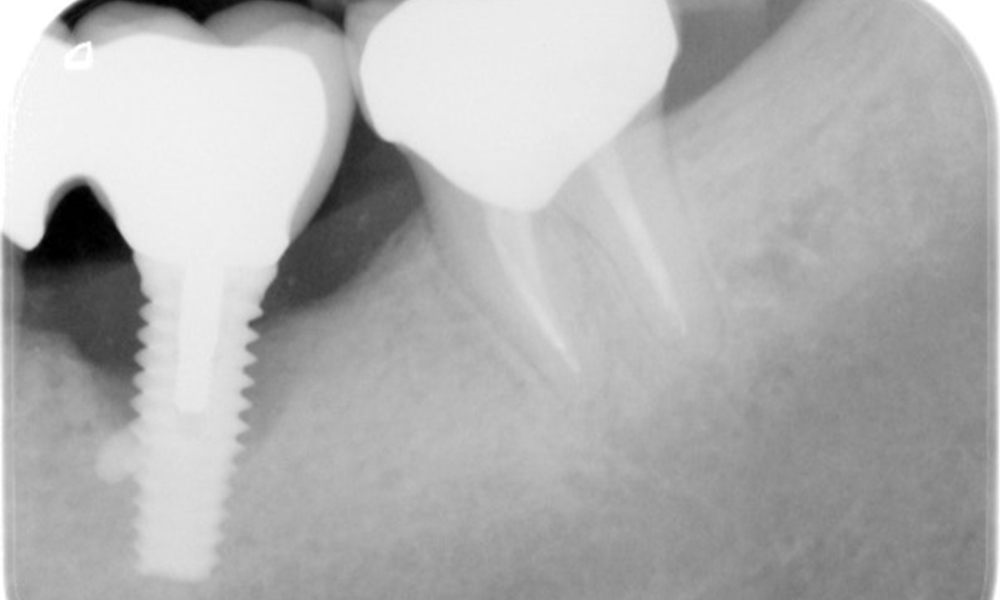

52-годишен пациент се явява на профилактичен преглед. Пациентът няма хронични заболявания и не приема никакви лекарства. Претърпял е различни дентални лечения и също така има две активни кариозни лезии. Освен това има четири импланта (2-ри, 3-ти и 4-ти квадрант). Установява се, че има ранно пародонтално заболяване (стадий IV, степен В). Състоянието на пародонта е стабилно, като дълбочина на сондиране (ST) от 5 mm се проявява само при импланта в област 36. Установен е и гингивит.

В историята на заболяването на пациента няма особени рискови фактори със специфични дентални последици. Следователно ключовият фактор е изискването по отношение на оралното здраве. В това отношение има данни за дълбочина на сондиране от 5 mm при импланта в 3-ти квадрант, а на рентгеновата снимка - за увеличена костна загуба. Пациентът също така има стабилно понастоящем пародонтално заболяване и две активни начални кариозни лезии.